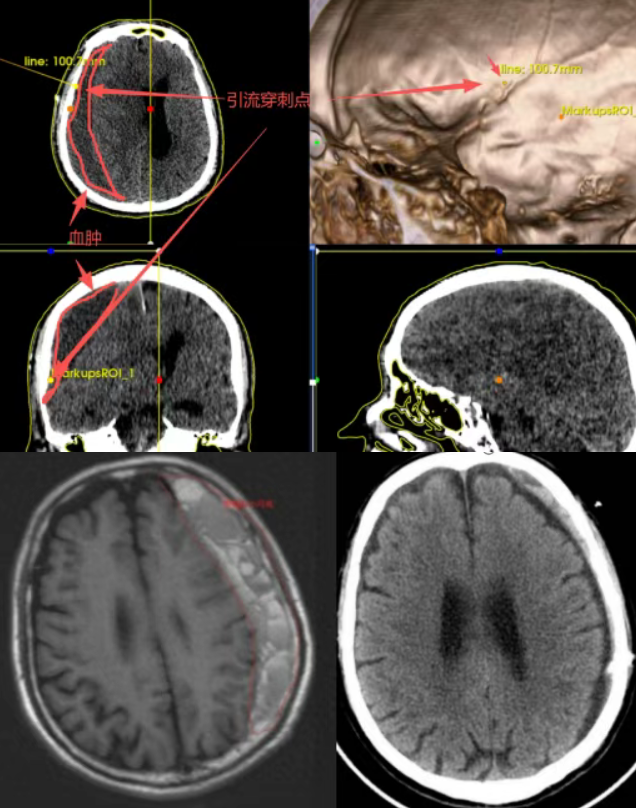

长沙市第四医院神经外科一病区通过术前高精度CT等影像进行三维重建与手术路径规划,可以在一次手术中,既完成血肿的充分引流,又将肇事的脑膜中动脉电凝闭塞减少复发。

(▲手术患者术前术后的影像学对比,显示血肿基本清除)